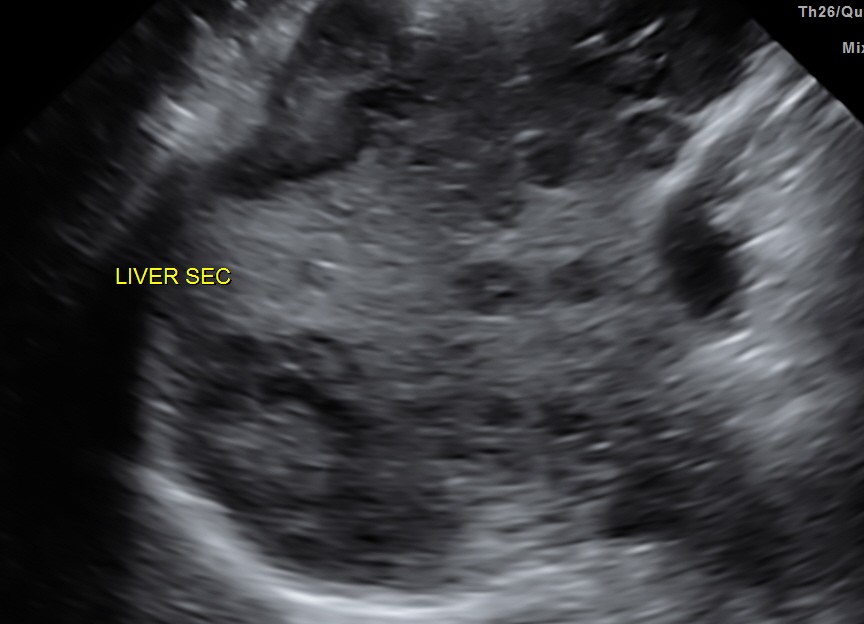

His liver showed multiple secondaries .

secondaries show target appearance or bird’s eye view of mexican hat appearance

DISCUSSION : Generally the target sign or the bird’s eye view of the Mexican hat sign could signify colo-rectal carcinoma.